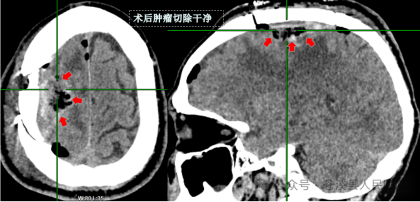

▲术后复查CT

手术当天,主刀医师通过术前三维重建,高清神经外科显微镜辅助,成功实施颅内肿瘤显微切除手术。术后患者头晕头痛、癫痫症状消失,无肢体及语言功能障碍,现已康复出院。术后病理回报:额叶大脑镰旁脑膜瘤。